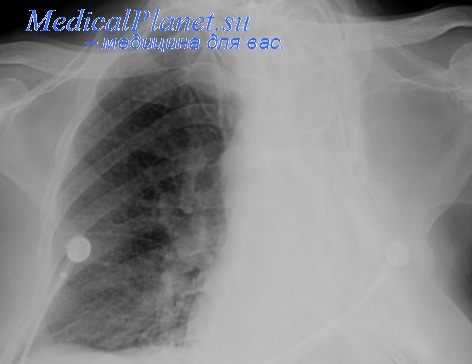

Рентгенологическая картина после торакопластики. На обзорных рентгенограммах и томограммах после экстраплевральной Т. определяется уменьшение объема оперированной половины грудной клетки и спадание соответствующего легкого. Степень уменьшения объема грудной клетки и легкого на оперированной стороне зависит от вида и объема Т. Рентгенологические изменения в легких наблюдаются при возникновении пневмонии, иногда осложняющей послеоперационное течение. В первые дни после операции могут возникать массивные ателектазы, в свою очередь осложняющиеся пневмониями. После обширной Т. может наблюдаться флотирование (маятникообразное смещение, синхронное с дыханием) средостения в области дефекта грудной стенки, исчезающее по мере регенерации костной ткани из оставшейся надкостницы ребер.

В отдаленные сроки после операции спавшееся легкое частично расправляется и вентиляция его улучшается за счет увеличения амплитуды дыхательных движений диафрагмы и ребер на стороне оперативного вмешательства, что отчетливо определяется на рентгенокимограмме (см. Рентгенокимография). В ряде случаев расправления легкого в отдаленные сроки не происходит вследствие развития в нем после операции пневмосклероза (см.), а иногда в последующем — бронхоэктазов (см.).

Определяемые после Т. тени регенерировавших ребер, особенно на фоне массивных плевральных шварт, затрудняют распознавание остаточных каверн и щелевидных остаточных полостей эмпием в случае неэффективной операции. Томография (см.) облегчает диагностику каверн в спавшемся легком, а фистулография (см.) и бронхография (см.) — выявление остаточных полостей.